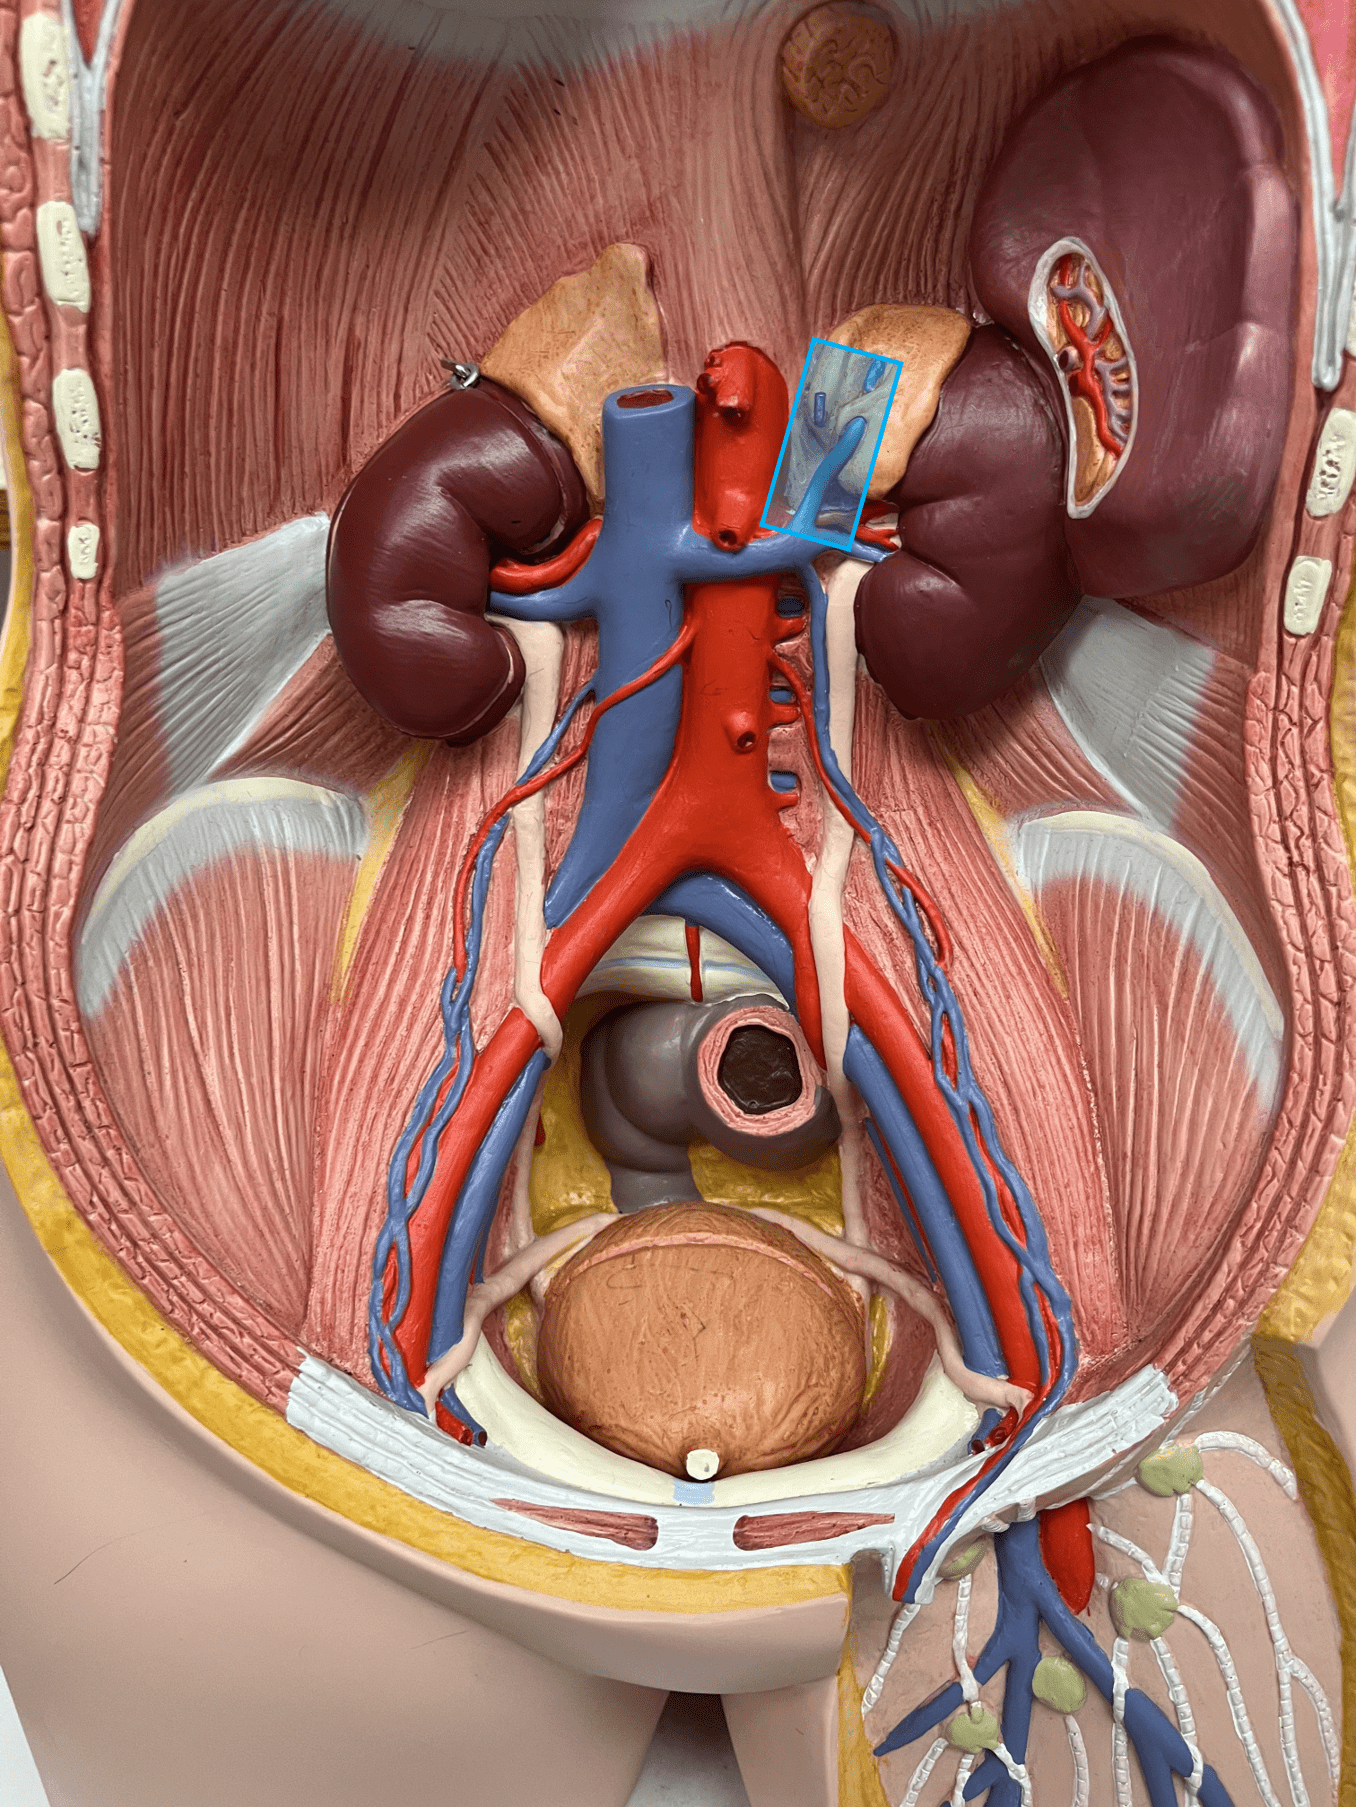

tunica media

renal vein

• A vein of the abdomen.

• Drains the kidneys.

• Empties into the inferior vena cava.

• On the inferior vena cava, inferior to the hepatic veins and superior to the gonadal veins.

• Drains the kidneys.

• Empties into the inferior vena cava.

• On the inferior vena cava, inferior to the hepatic veins and superior to the gonadal veins.